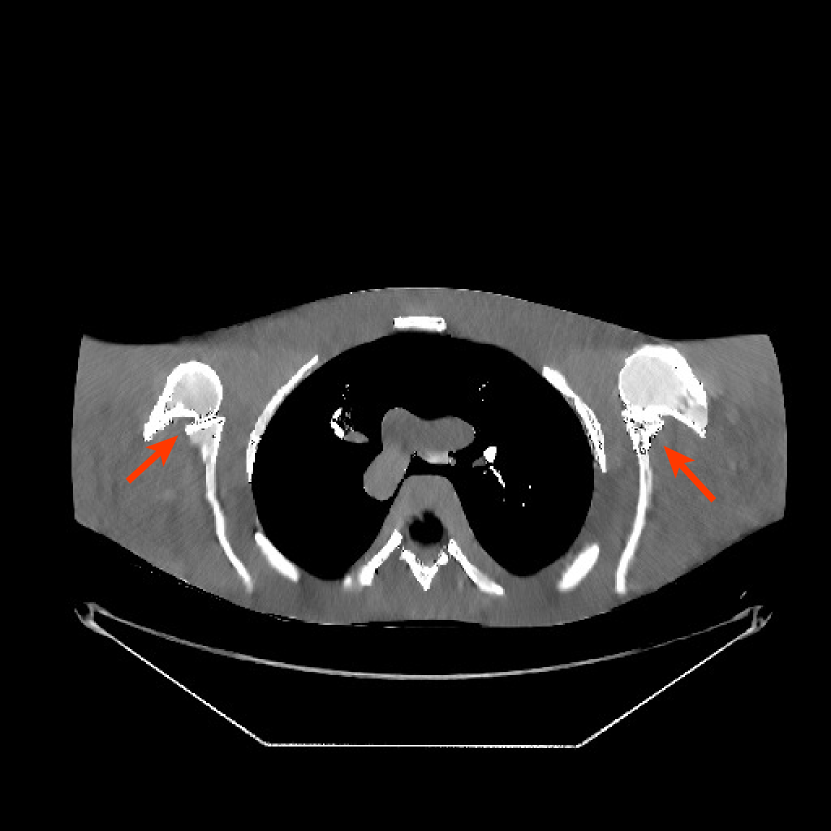

Refer to caption

Figure 10: Reconstructions for ultra low-dose 2D scan simulated from raw measurements. The leftmost image is the PWLS-EP reconstructed image for the 200 mA200 mA200\text{ mA} scan. The second image is the PWLS-EP reconstruction for the simulated ultra low-dose scan, and it is the initial image for WavResNet [46], PWLS-ULTRA [38], and SPULTRA. The display windows are [800, 1400] HU.

V-C2 Results

Fig. 10 shows the reconstructions for the 200 mA200 mA200\text{ mA} scan (reference image) along with the reconstructions for the simulated ultra low-dose scan obtained with PWLS-EP, WavResNet, PWLS-ULTRA, and SPULTRA. Visually, WavResNet fails to reconstruct the image but improves over the initial PWLS-EP reconstruction, while PWLS-ULTRA and SPULTRA provide better image quality. This indicates that the ULTRA-based methods may have a better generalization property than WavResNet, since they learn more fundamental features of CT images (also see [38]). We selected three smooth ROIs, where the pixel values are approximately constant. Tab. V(b) shows the mean and the standard deviation of pixel values for these ROIs for various methods and the standard-dose reference. Since the iterative RNN version of WavResNet only has small improvements over PWLS-EP, the pixel values do not change much compared with PWLS-EP. PWLS-ULTRA however reduces the bias in the central region of the image (ROI 2), but fails to correct the bias in the regions near the bones (ROI 1 and ROI 3). SPULTRA reduces the bias in the central region of the image, and also significantly corrects the bias near the bone regions. The standard deviations of the ROIs reconstructed by SPULTRA are comparable to those reconstructed by PWLS-ULTRA, and are close to those of the reference ROIs. Additionally, SPULTRA reconstructs the bone (indicated by the magenta arrow in the last two subfigures of Fig. 10) better than PWLS-ULTRA.